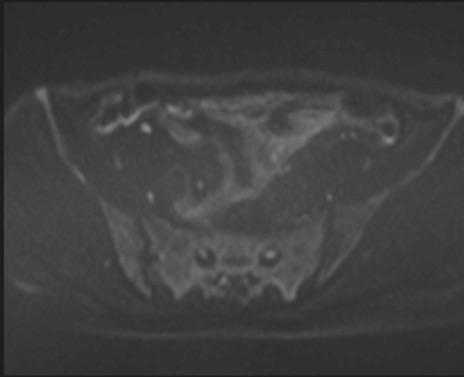

症例39 DWI/ADC

MRI(4日後)